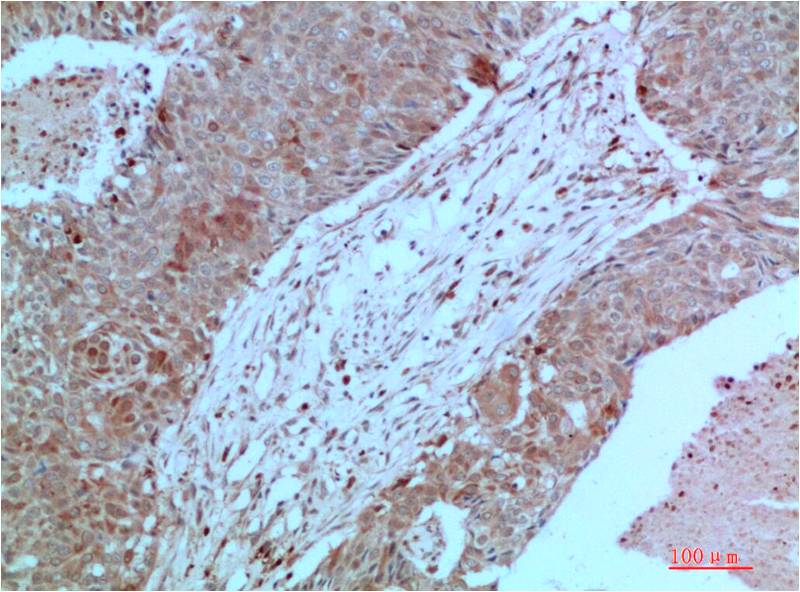

- Immunohistochemistry analysis of paraffin-embedded Human Lung Carcinoma Tissue using JAK2 antibody.High-pressure and temperature Sodium Citrate pH 6.0 was used for antigen retrieval.